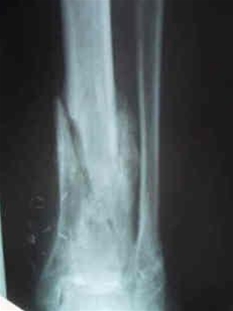

Et almindeligt røntgenbillede viser som regel ikke forandringer før efter 1-2 uger. Skintigrafi og MR-skanning kan imidlertid vise forandringer forholdsvis tidligt.

Det kan være relevant at tage vævsprøver ud fra det betændte knoglevæv for at finde ud af, hvilken bakterie der er årsag til infektionen. Det gøres ved at tage en prøve i det betændte væv, ofte under vejledning af CT-skanning, MR-skanning eller røntgen-undersøgelser. I visse tilfælde findes bakterien ved hjælp af blodprøverne.